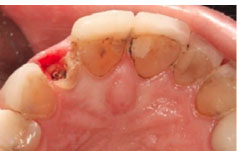

Figure 2.

The fractured maxillary lateral incisor.